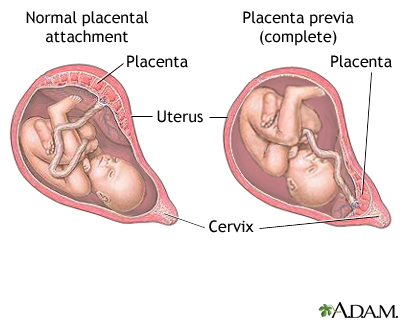

Placenta previa is a problem of pregnancy in which the placenta grows in the lowest part of the womb (uterus) and covers all or part of the opening to the cervix.

During pregnancy, the placenta moves as the womb stretches and grows. It is very common for the placenta to be low in the womb in early pregnancy. But as the pregnancy continues, the placenta moves to the top of the womb. By the third trimester, the placenta should be near the top of the womb, so the cervix is open for delivery.

Sometimes, the placenta partly or completely covers the cervix. This is called a placenta previa.

There are different forms of placenta previa:

- Marginal: The placenta is next to the cervix but does not cover the opening.

- Partial: The placenta covers part of the cervical opening.

- Complete: The placenta covers all of the cervical opening.